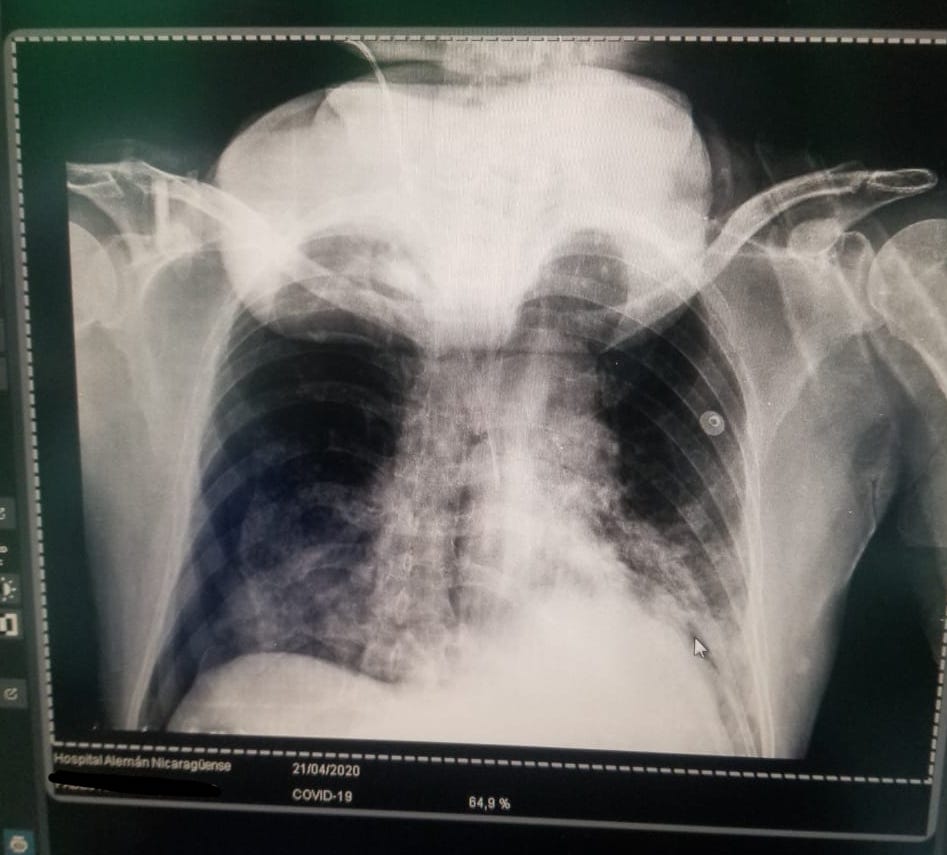

Un mes más tarde, con el pico de contagios en su etapa más álgida, y con la dificultad de matizarlos ante tantos entierros, la vicepresidenta Rosario Murillo admitió un aumento del 54% de muertes por neumonía. Sin embargo, no las asoció al coronavirus. En aquel momento, DIVERGENTES recopiló con fuentes médicas más de cincuenta radiografías de pulmón de diversos hospitales del país, en la que los casos neumónicos eran evidentes. Los doctores aseguraron que no les cabía duda de que se trataban de casos de COVID-19, pero la mordaza impuesta por la autoridad sanitaria y la centralización de las pruebas impedían alertar a los familiares de los contagiados. Médicos sostienen que haber minimizado el impacto de la pandemia, generó más contagios y muertes.